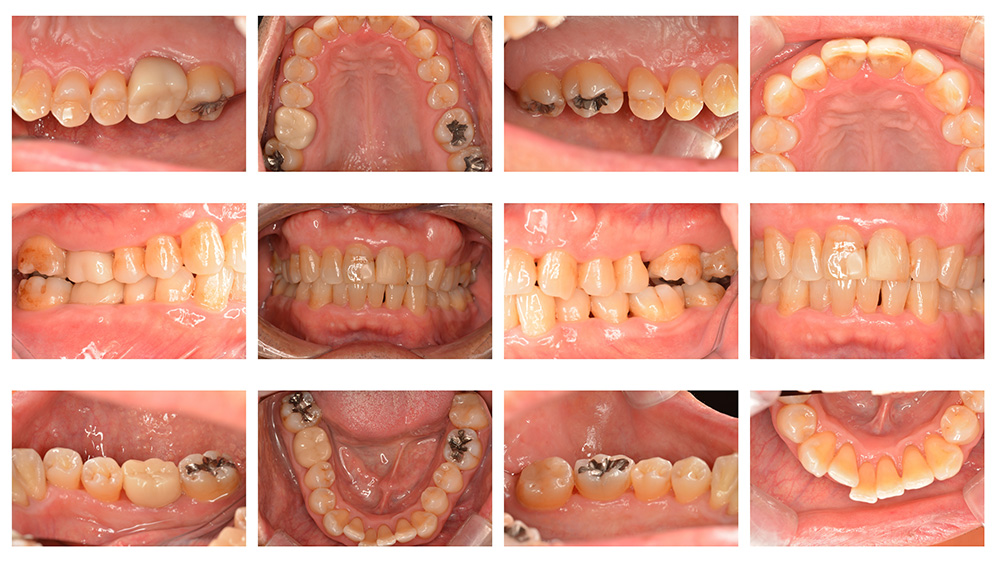

術前

術後

世代・性別

40代女性

主訴

歯が揺れている気がするので見てほしい

治療内容

ブラッシング指導、歯周基本治療

治療期間

4ヶ月

治療費

保険適応内

治療のリスク

一時的に歯ぐきからの出血や痛み、歯のしみ(知覚過敏)が起こることがある